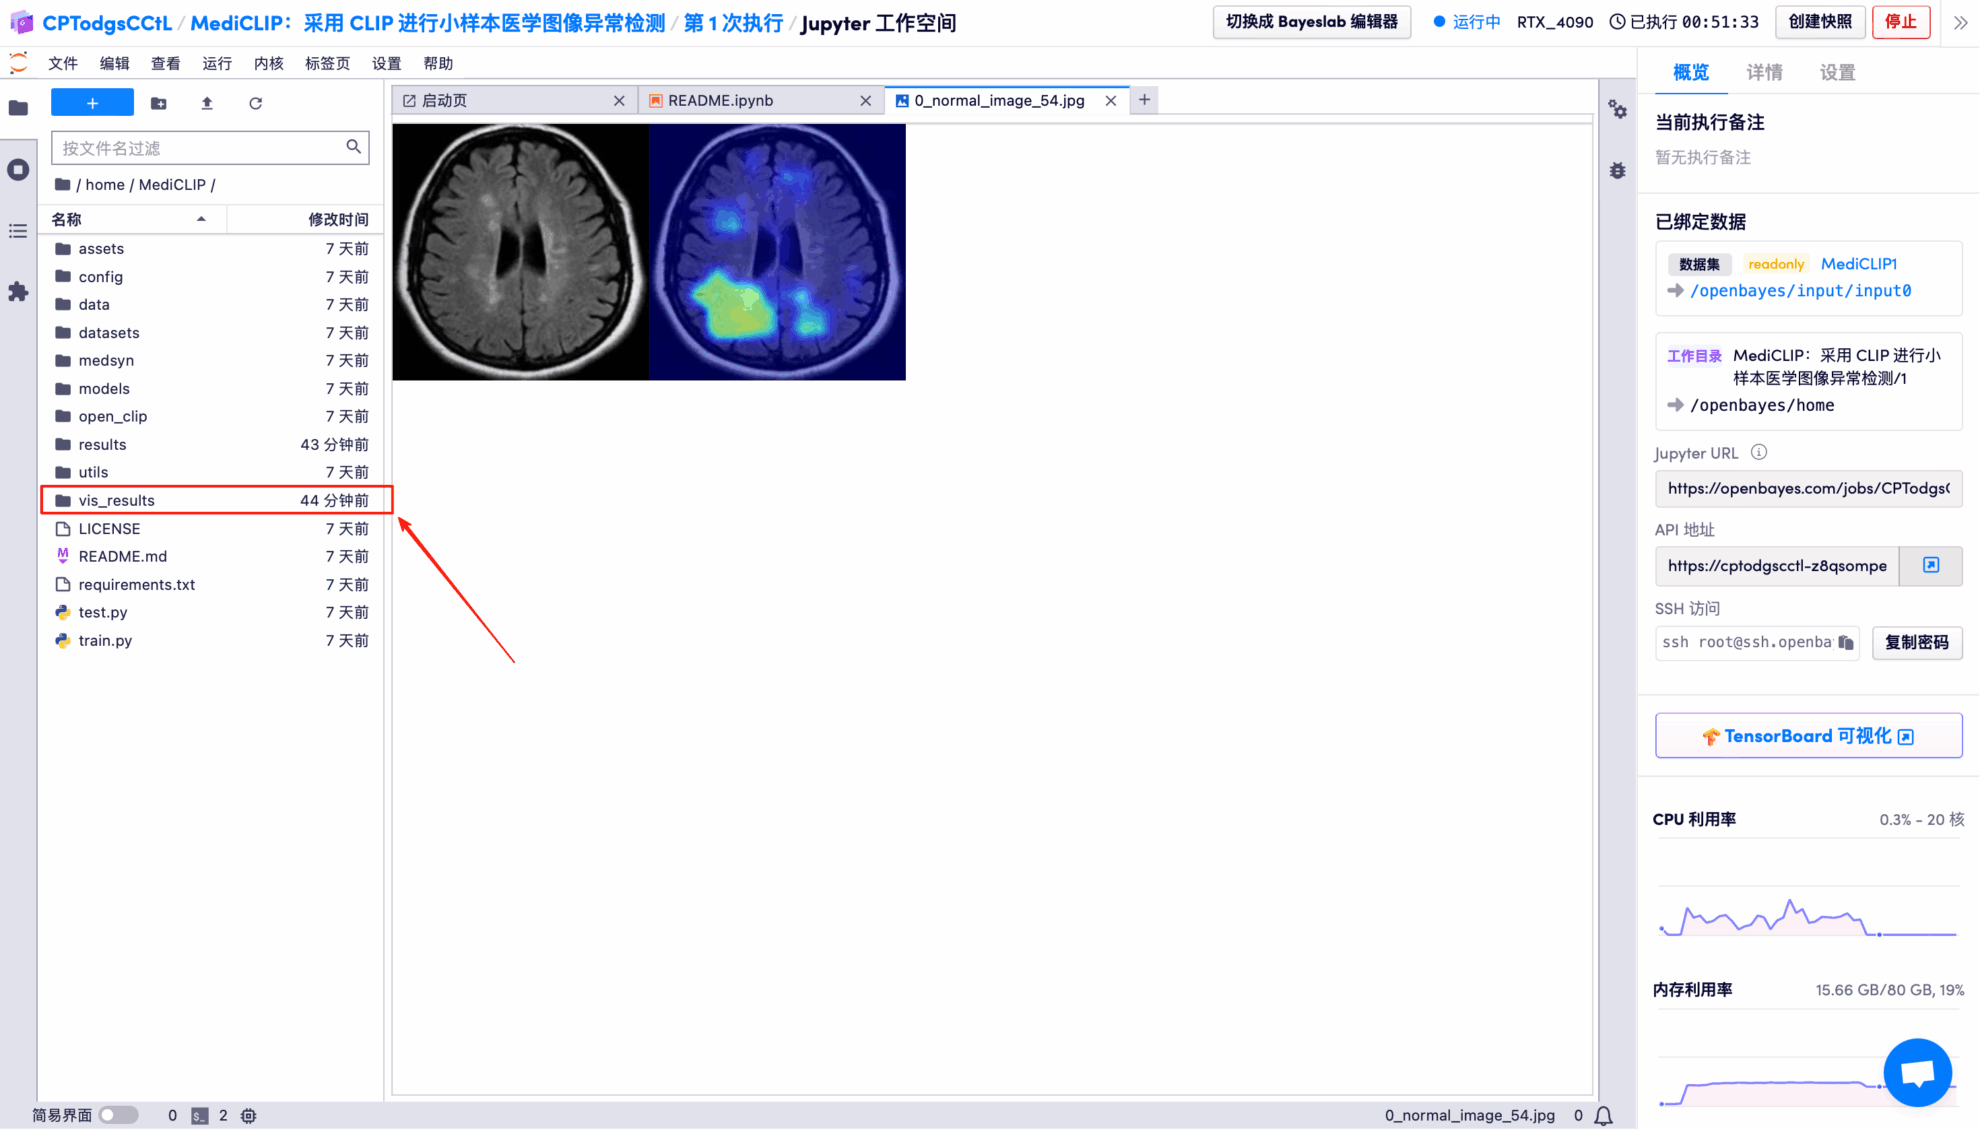

The model's visual detection results for each test image are saved to the openbayes//home/MediCLIP/vis_result directory by default. The specific location is shown in the figure below:

Randomly open a test result picture, which is clearly and intuitively displayed:

* Left: Original brain image

* Right: Highlighted "abnormal area"